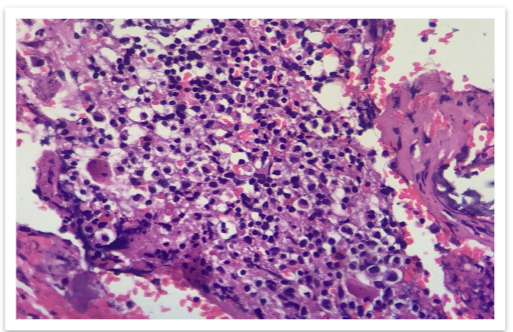

The MRI findings showed multiple focal altered signal intensity lesions (Figure 2). A bone biopsy was performed, and histopathological examination revealed the presence of plasma cells.

Immunohistochemistry showed plasmacytoid cells are positive for CD 138 (Figure 6). The patient was diagnosed with non-secretory multiple myeloma.